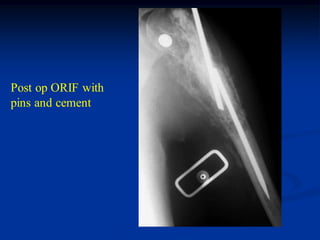

Post op ORIF with

pins and cement